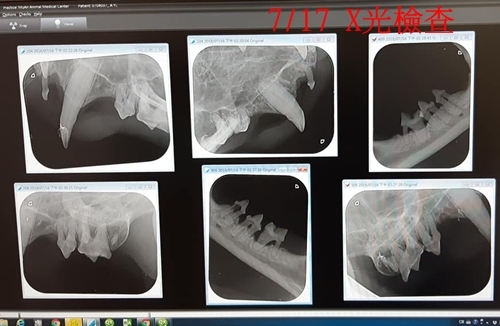

阿義平時的健康狀況還不錯,還是協會的捐血小英雄,在2018年4月時因為要捐血救水腎的小居,到醫院進行血型配對的檢查時發現有牙齦炎,及部份牙齒槽骨往下掉使得牙齒搖動,因此在7/9先至醫院做檢查,照X光、血檢,以確定進行手術的事宜,經醫師評估後,於7/17進行了牙周手術,照全口X光、拔除10幾顆牙、洗牙,醫生並叮嚀阿義的呼吸聲有些大,x光片看到肺部有些發炎,須要留意。

口腔部分,初步看來有幾顆牙是壞掉的,有牙齦炎沒有口炎症狀,牙齒部分清理或拔除後發炎會有改善,排時間照X光,等拍照後,才能確認那些牙是需要拔除的。

阿義的上呼吸道聲音有點大,從X光片上看來肺部是有些慢性發炎的現象,但看起來沒有嚴重到不能麻醉,麻醉後咳嗽頻率會增加一些,術後會再加開一些化痰藥,其他還好,腎指數有微微上升(GLOB5.3),但還在安全值內,(X光片上剛好有拍到腎臟,腎臟看起來正常沒問題)球蛋白和白血球較高的部分,等處理完牙齒部分,再看看有無恢復正常,血小板紅血球都正常,下禮拜一安排洗牙拔牙。

1. 牙齒X光顯示阿義牙齒的槽骨往下掉,使得牙齒會搖動,很多顆牙齒狀況不好,所以拔了10幾顆牙,有四處縫皮瓣。8點時可以喝水,沒有咳或嘔吐,半小時候給軟食。

2. 前次7/9回診時,阿義的上呼吸道聲音有點大,當時從X光片上看來肺部是有些慢性發炎的現象,今天麻醉插管時有很多痰,有可能是肺部感染,今天會開化痰藥。